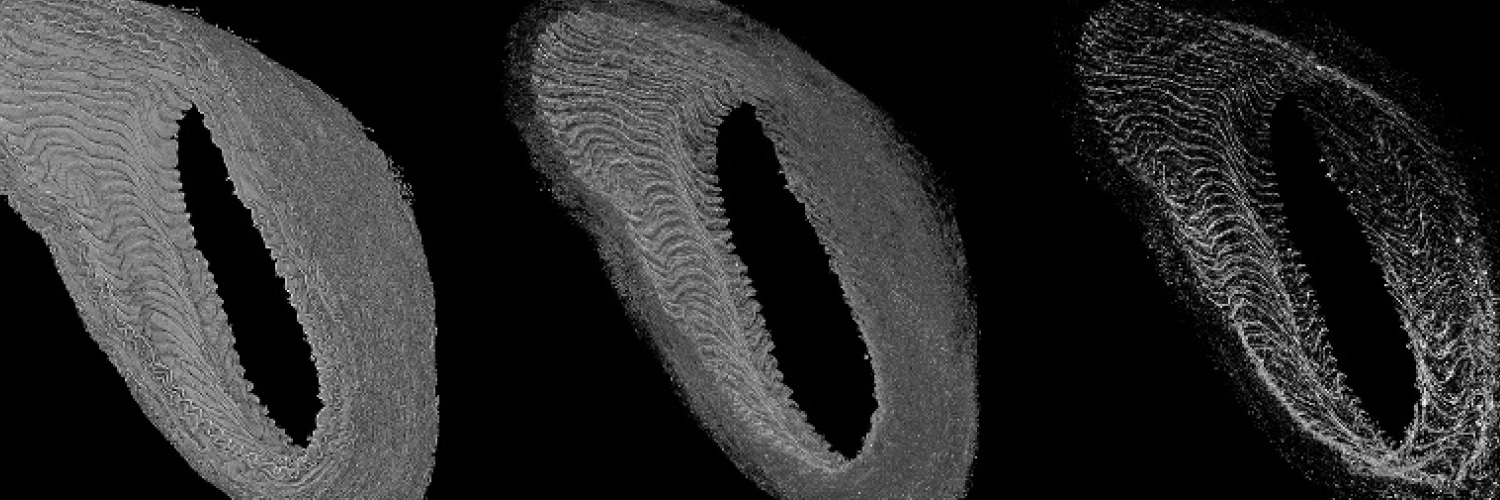

Les champs d'expertise numérique de l'équipe reposent sur les champs suivants : intelligence artificielle, image, analyse exploratoire de données, observabilité des données, analyse multiéchelle, morphologie mathématique, topologie discrète, filtrage spatio-fréquentiel, analyse dynamique, classification, décision, mesure de similarité, détection de changements, modélisation statistique.

Les champs d'expertise clinique de l'équipe reposent sur les modalités suivantes : imagerie par résonance magnétique (IRM), scanner (TDM), artériographie, imagerie nucléaire (TEP, TEMP), électroencéphalographie (EEG), échographie, imagerie préclinique (synchrotron). Les domaines cliniques privilégiés sont la néonatologie, la cancérologie, la neurologie, la radiologie, l'endocrinologie, l'urologie, l'histopathologie.